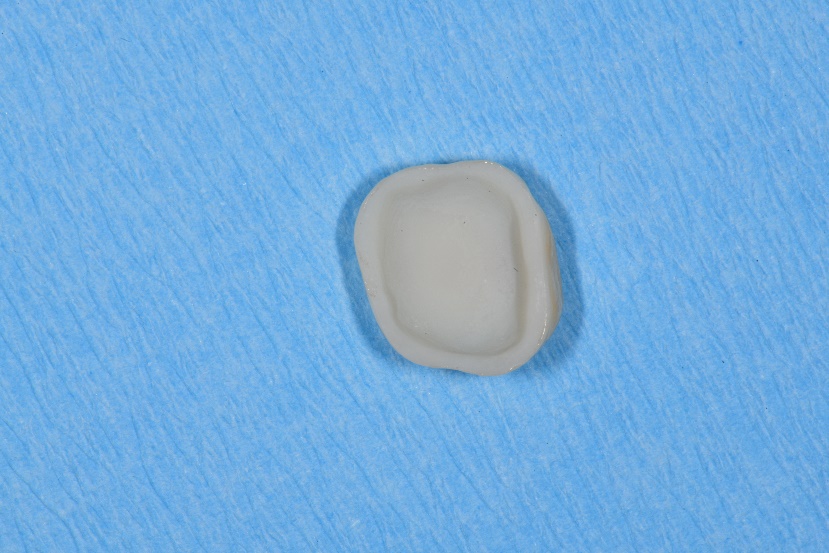

Occlusal view of the finalized crown of tooth 16. Fissures were individualized with stains.

Occlusal view of the finalized crown of tooth 26. Fissures were individualized with stains.

Basal view of crown 16 before conditioning with hydrofluoric acid.

Basal view of crown 16 after conditioning with hydrofluoric acid for 30 seconds.